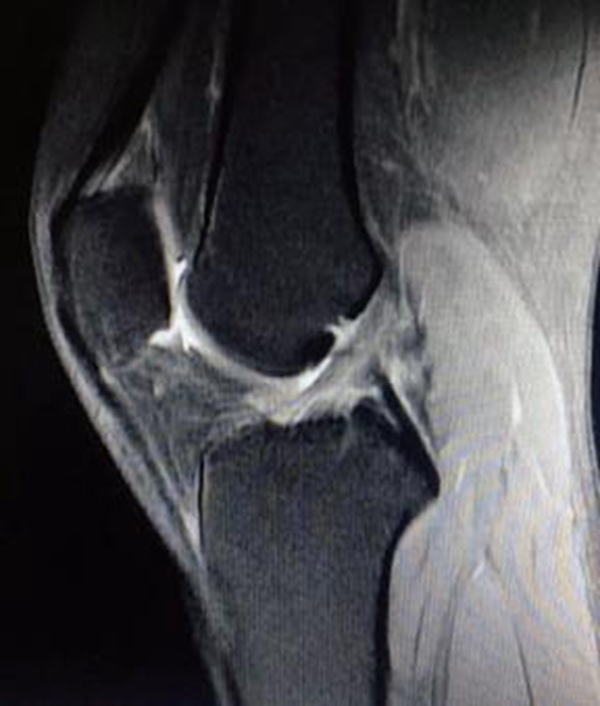

由于ACL的解剖特点,常规MRI扫描方向无法满足精确诊断的需要,因此沿ACL的方向扫描对于诊断有重要的作用。MRI影像上正常的ACL是起自股骨外侧髁内侧面,斜向前内侧走行,止于胫骨髁间隆起前方的一条边缘清晰、光滑、具有张力感的低信号带(图7)。连续性中断是ACL断裂最直观的表现(图8)。

Lee等提出ACL断裂的MRI诊断标准: ①ACL前缘呈不规则波浪状;②T2WI成像中ACL信号内有高信号;③矢状面上ACL信号不连续;④当伴有上述征象之一时,前部呈弓状的PCL可支持ACL撕裂。

图7 正常ACL的MRI影像

图8 ACL断裂MRI影像